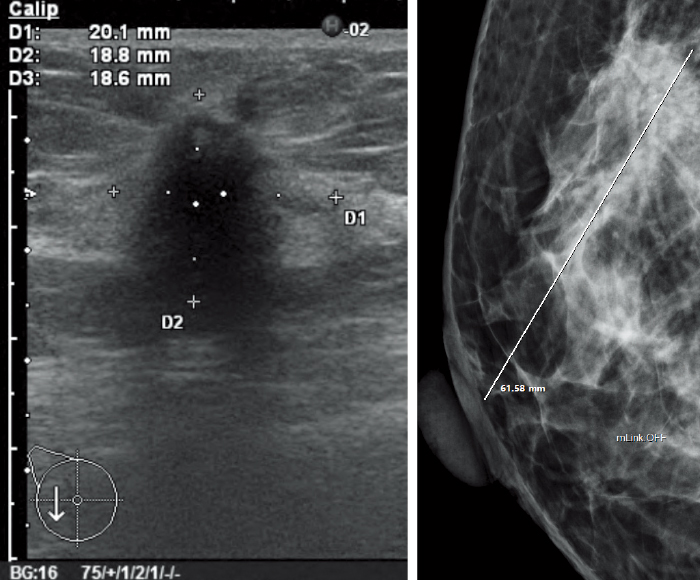

Various images, such as MG, BT, MR, CT, US, etc., are available for mammography diagnosis at the same time.

Values for ROI and X-ray gauging can be obtained from the information in each imaging modality.

ROI (Region of interest)